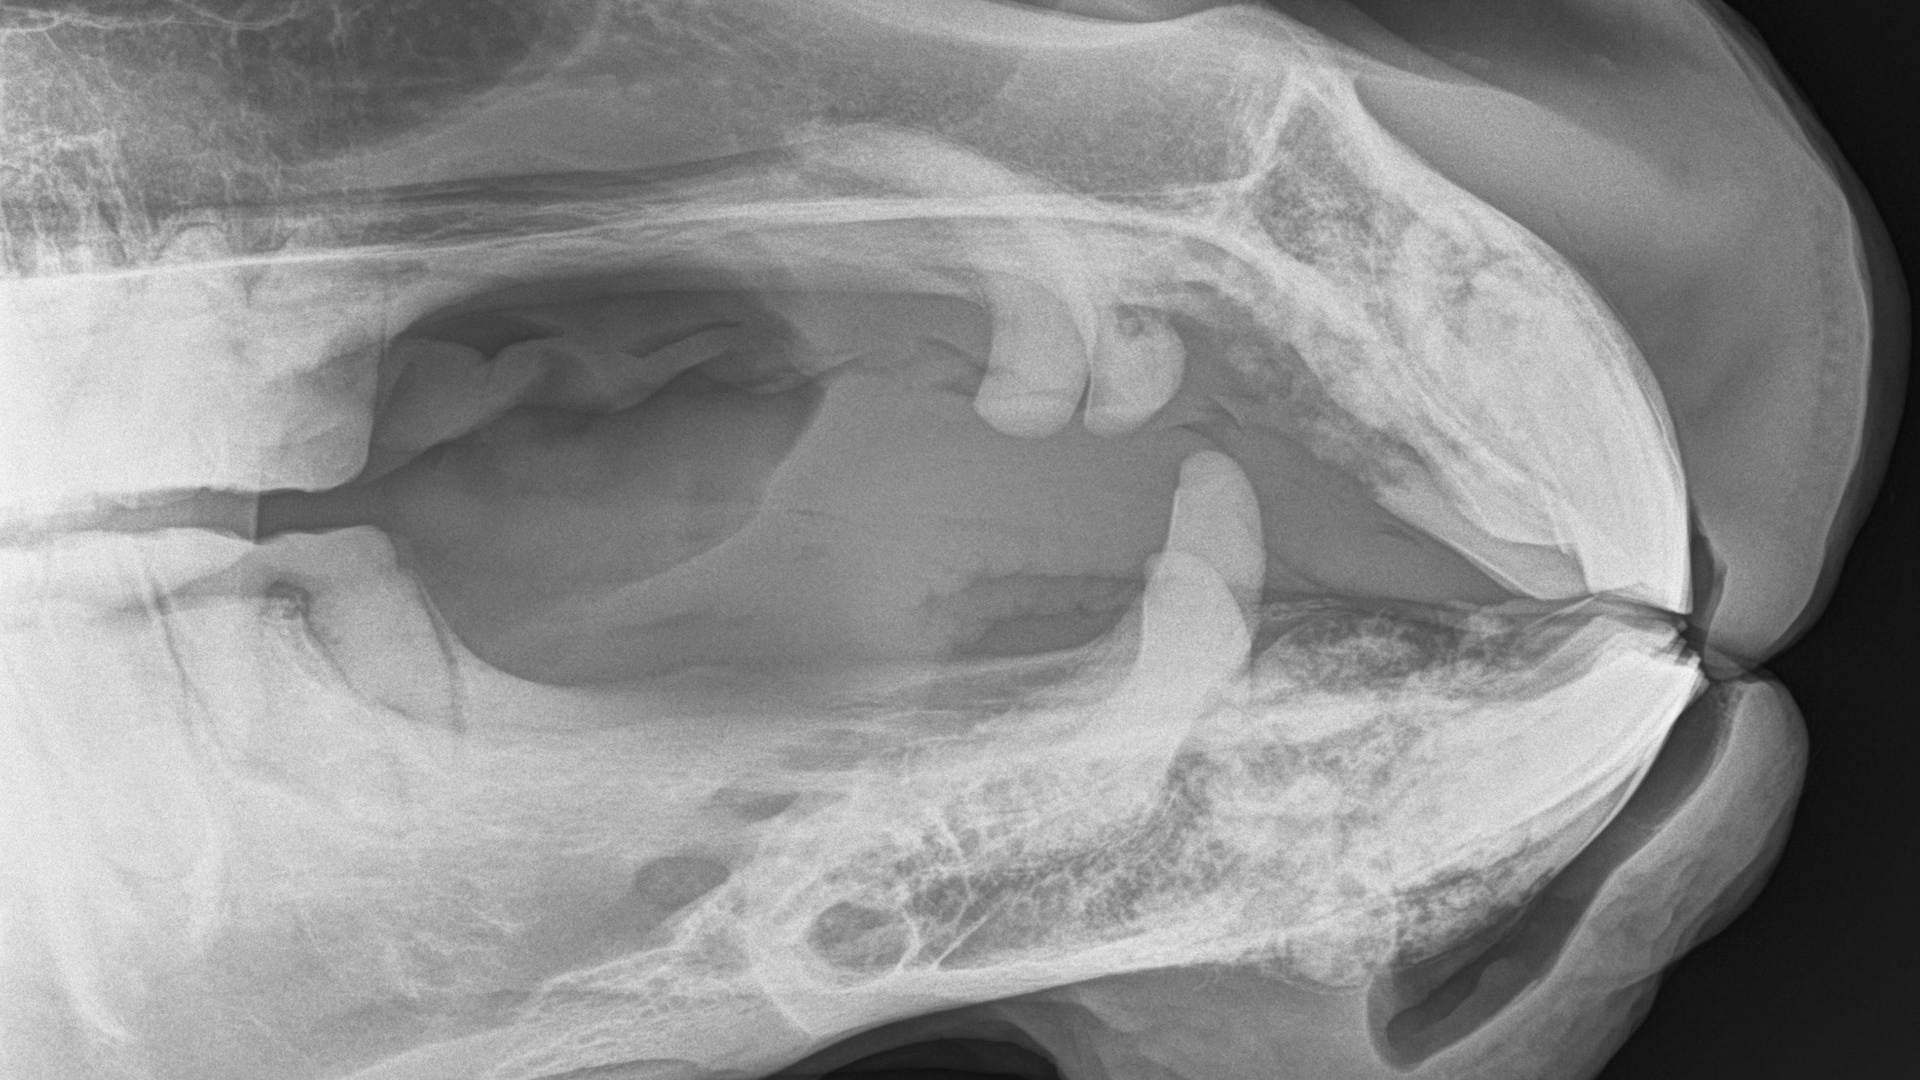

A radiograph (X-ray) of the canines and incisor teeth in a horse with EOTRH. Note the lacy look of the bone where the teeth insert as well as the enlargement of the tooth roots as they struggle to hang on.